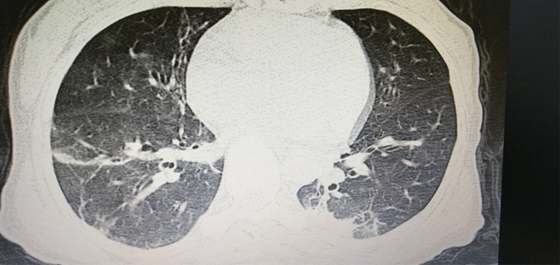

经治疗患者“白肺”得到明显改善

向开旺医生立即为马女士实施了纤维支气管镜检查,通过肺泡灌洗液高通量测序技术也发现“鹦鹉热衣原体”,真相水落石出。明确了病因,在针对病原菌治疗后,马女士很快退热,“白肺”得到明显改善,病情逐渐好转,经过重症医学科医护团队21天的精心照护,最终康复出院。